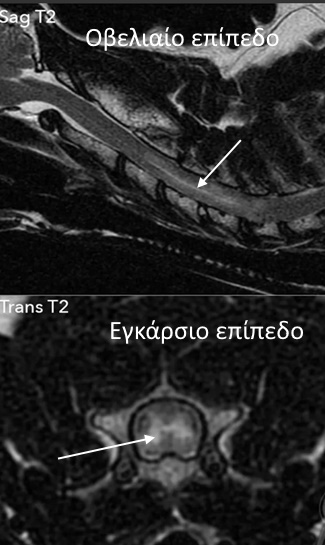

Τα κλασικά ευρήματα της MRI περιλαμβάνουν καλά περιγεγραμμένη, συνήθως ασύμμετρη, ενδομυελική αλλοίωση που έχει σήμα αυξημένης έντασης (φαίνεται λευκή) στη Τ2 ακολουθία, είναι ισοεντατική στη Τ1 ακολουθία και εμφανίζεται με ελάχιστη ή καθόλου ενίσχυση σκιαγραφικού (“blush pattern”) στην Τ1 ακολουθία μετά τη χορήγηση γαδολινίου.

MRI αυχενικής μοίρας, Τ2 ακολουθία σε σκύλο με ινοχόνδρινο έμβολο στα νευροτόμια Α3 έως Α6. Διακρίνεται η καλά περιγεγραμμένη ενδομυελική αλλοίωση με σήμα αυξημένης έντασης (βέλος).